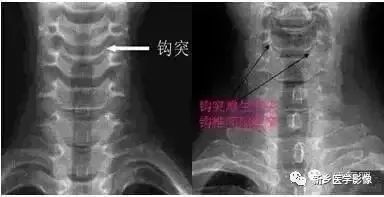

三钩突:钩突:正位片钩突呈三角形,钩椎关节宽约2mm;侧位片呈扇形,占椎体上缘后段的1/3~1/2;斜位片在椎间孔的前下方。钩椎关节退变在X片上表现为关节间隙变窄(小于2mm)和钩突的肥大、增生或尖刺状增生。

钩椎关节的重要毗邻:后方为脊髓、脊膜支和椎体的血管;后外侧部构成椎间孔的前壁,邻接颈神经根;外侧有椎动静脉和交感神经丛。

正常 退变变窄